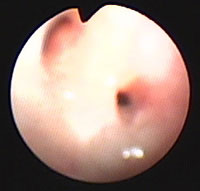

気管支鏡検査:第12病日に行った。肉眼所見で、肺内気管支粘膜に浮腫・軽度発赤あり(図5)、BAL[RB3, 10ml×3, 回収率77.3%]に好酸球数の増加(33.2%)とマクロファージの活性化がみられ(図6)、培養にて細菌も真菌も検出されなかった。

図5 症例2の気管支鏡検査所見。肺内気管支粘膜に浮腫・軽度発赤がみられた。